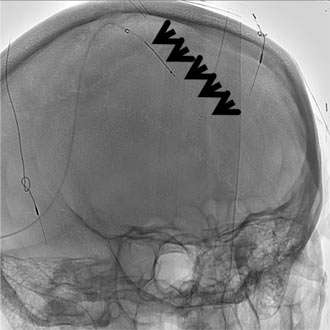

Anticoagulation, the administration of a blood thinning drug is the first line of treatment and has been shown to be very effective. However, when the clot burden is too large and/or the patient condition deteriorates despite anticoagulation treatment, catheter based clot-busting treatment becomes a consideration (Figure 3).

Using the state-of-the-art interventional suite equipped with the latest biplane X-ray machine, we can safely navigate a catheter into the cerebral venous sinus that is blocked with the clot. Via the catheter, we can deploy a clot-capturing device or aspirate the clot from the catheter itself.